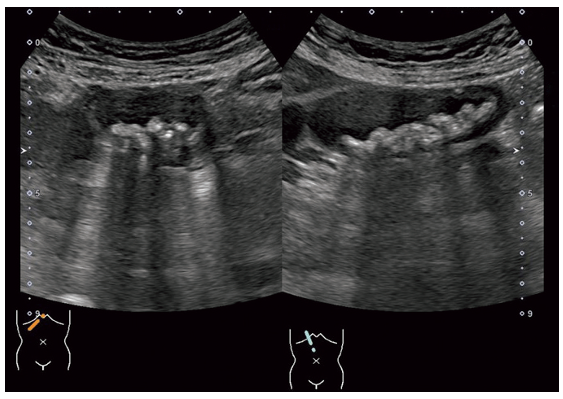

胆囊の超音波像を示す。

考えられる疾患はどれか。

- 胆泥

- 胆囊結石

- 壁内結石

- 胆囊腺筋腫症

- コレステロールポリープ

解説

胆嚢内に高エコーの丸い複数の固形物であることから、選択肢内から胆嚢結石と考えられる

答え 2